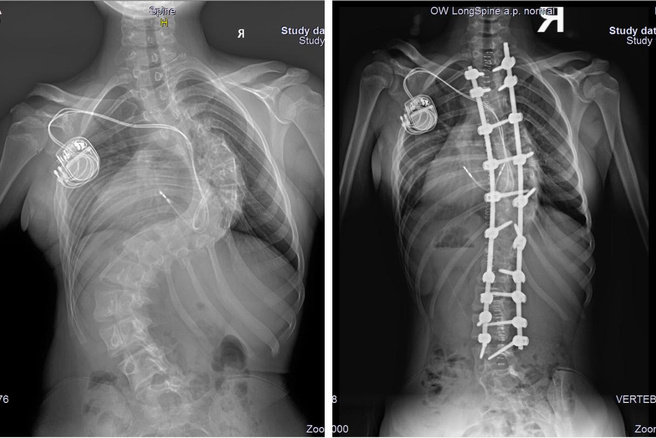

Сколиоз 19 Градусов Фото

Сколиоз 19 Градусов Фото 130 фото